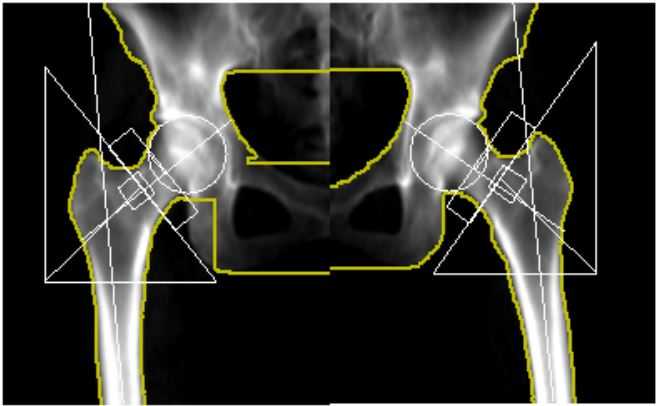

股間節の骨密度解析画像 |

人工股関節置換術を受けた患者さんは、骨密度の変化が局所的に発生することがあります。そのため、人工股関節の周囲をいくつかの領域(ゾーン)に分け、それぞれのゾーンごとに骨密度を測定し評価することで、どの部位で骨密度が低下しているかを明確にすることができます。骨密度が特定の部位で顕著に低下している場合、それに対して予防や治療が行いやすくなります。